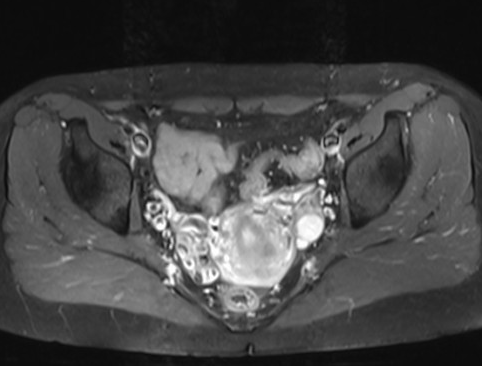

2.增强CT及MRI检查

可显示子宫附件内迂曲、扩张的静脉血管结构。